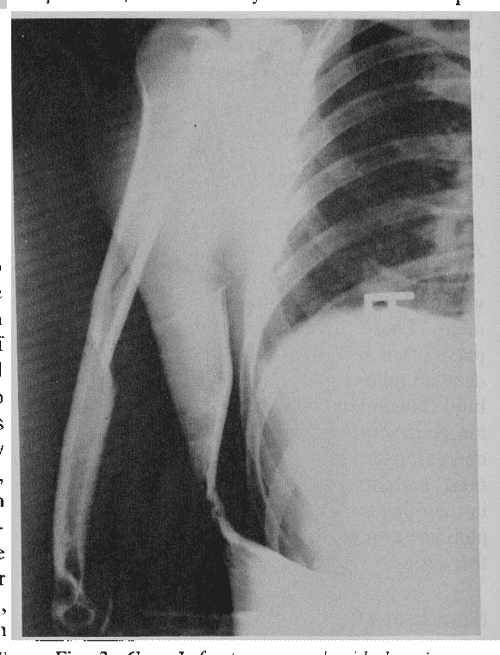

Spiral Fracture Humerus Arm Wrestling . The most common arm wrestling injury in adults is humeral shaft fracture. The most common injury associated with arm wrestling was spiral fractures of the distal part of the humerus. Humeral shaft fractures are the most common injury sustained in arm wrestling, and its various biomechanical, anatomical,. The dominant side is invariably affected. Of 93 patients who presented between 2009 and. Spiral fractures of the distal third of the humerus are by far the most common injury reported in the setting of arm wrestling. The most common arm wrestling injury in adults is humeral shaft fracture. Torsion and bending loads cause the humerus to fail. This study aimed to elucidate the current. The most common injury associated with arm wrestling was spiral fractures of the distal part of the humerus. The humerus fails due torsional and bending stresses. Arm wrestling is an important cause of humerus shaft fracture. In this series all fractures. This study aimed to elucidate the current. A spiral distal humeral shaft fracture is an unusual but significant injury that can result.

A spiral distal humeral shaft fracture is an unusual but significant injury that can result. Of 93 patients who presented between 2009 and. Humeral shaft fractures are the most common injury sustained in arm wrestling, and its various biomechanical, anatomical,. The humerus fails due torsional and bending stresses. The dominant side is invariably affected. In this series all fractures. The most common injury associated with arm wrestling was spiral fractures of the distal part of the humerus. Spiral fractures of the distal third of the humerus are by far the most common injury reported in the setting of arm wrestling. Torsion and bending loads cause the humerus to fail. The most common arm wrestling injury in adults is humeral shaft fracture.

Spiral Fracture Humerus Arm Wrestling The most common injury associated with arm wrestling was spiral fractures of the distal part of the humerus. The most common injury associated with arm wrestling was spiral fractures of the distal part of the humerus. The dominant side is invariably affected. Humeral shaft fractures are the most common injury sustained in arm wrestling, and its various biomechanical, anatomical,. Arm wrestling is an important cause of humerus shaft fracture. The most common injury associated with arm wrestling was spiral fractures of the distal part of the humerus. The most common arm wrestling injury in adults is humeral shaft fracture. The humerus fails due torsional and bending stresses. A spiral distal humeral shaft fracture is an unusual but significant injury that can result. This study aimed to elucidate the current. The most common arm wrestling injury in adults is humeral shaft fracture. Torsion and bending loads cause the humerus to fail. Spiral fractures of the distal third of the humerus are by far the most common injury reported in the setting of arm wrestling. In this series all fractures. Of 93 patients who presented between 2009 and. This study aimed to elucidate the current.